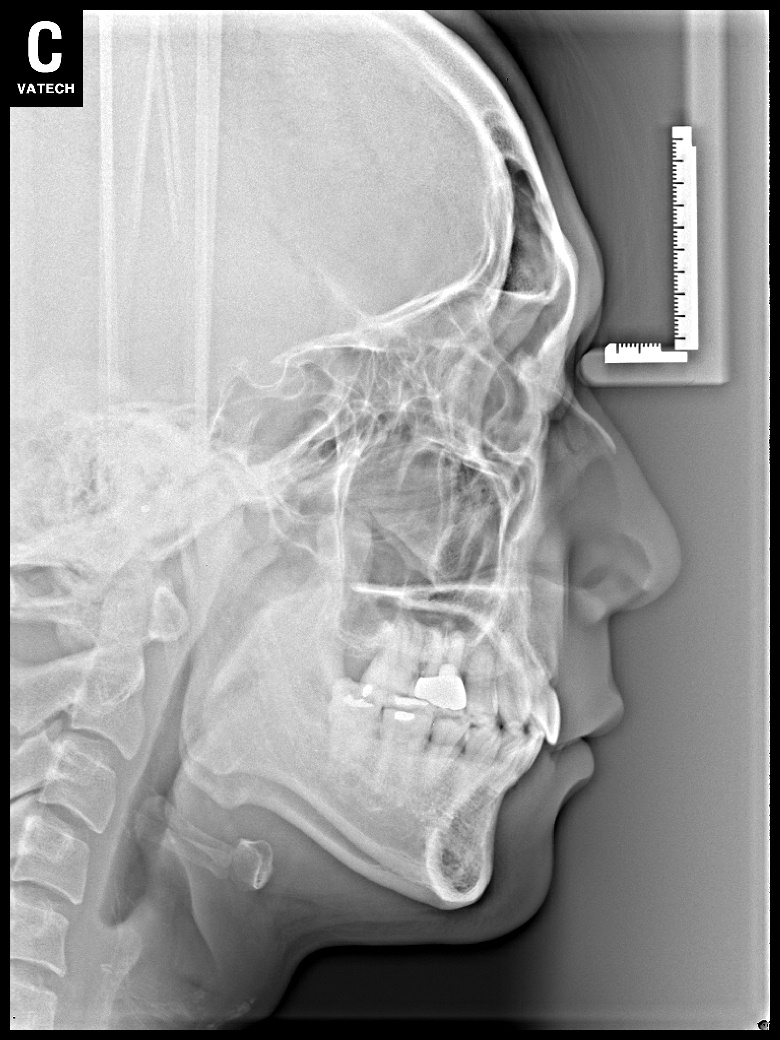

치료 전 사진입니다.